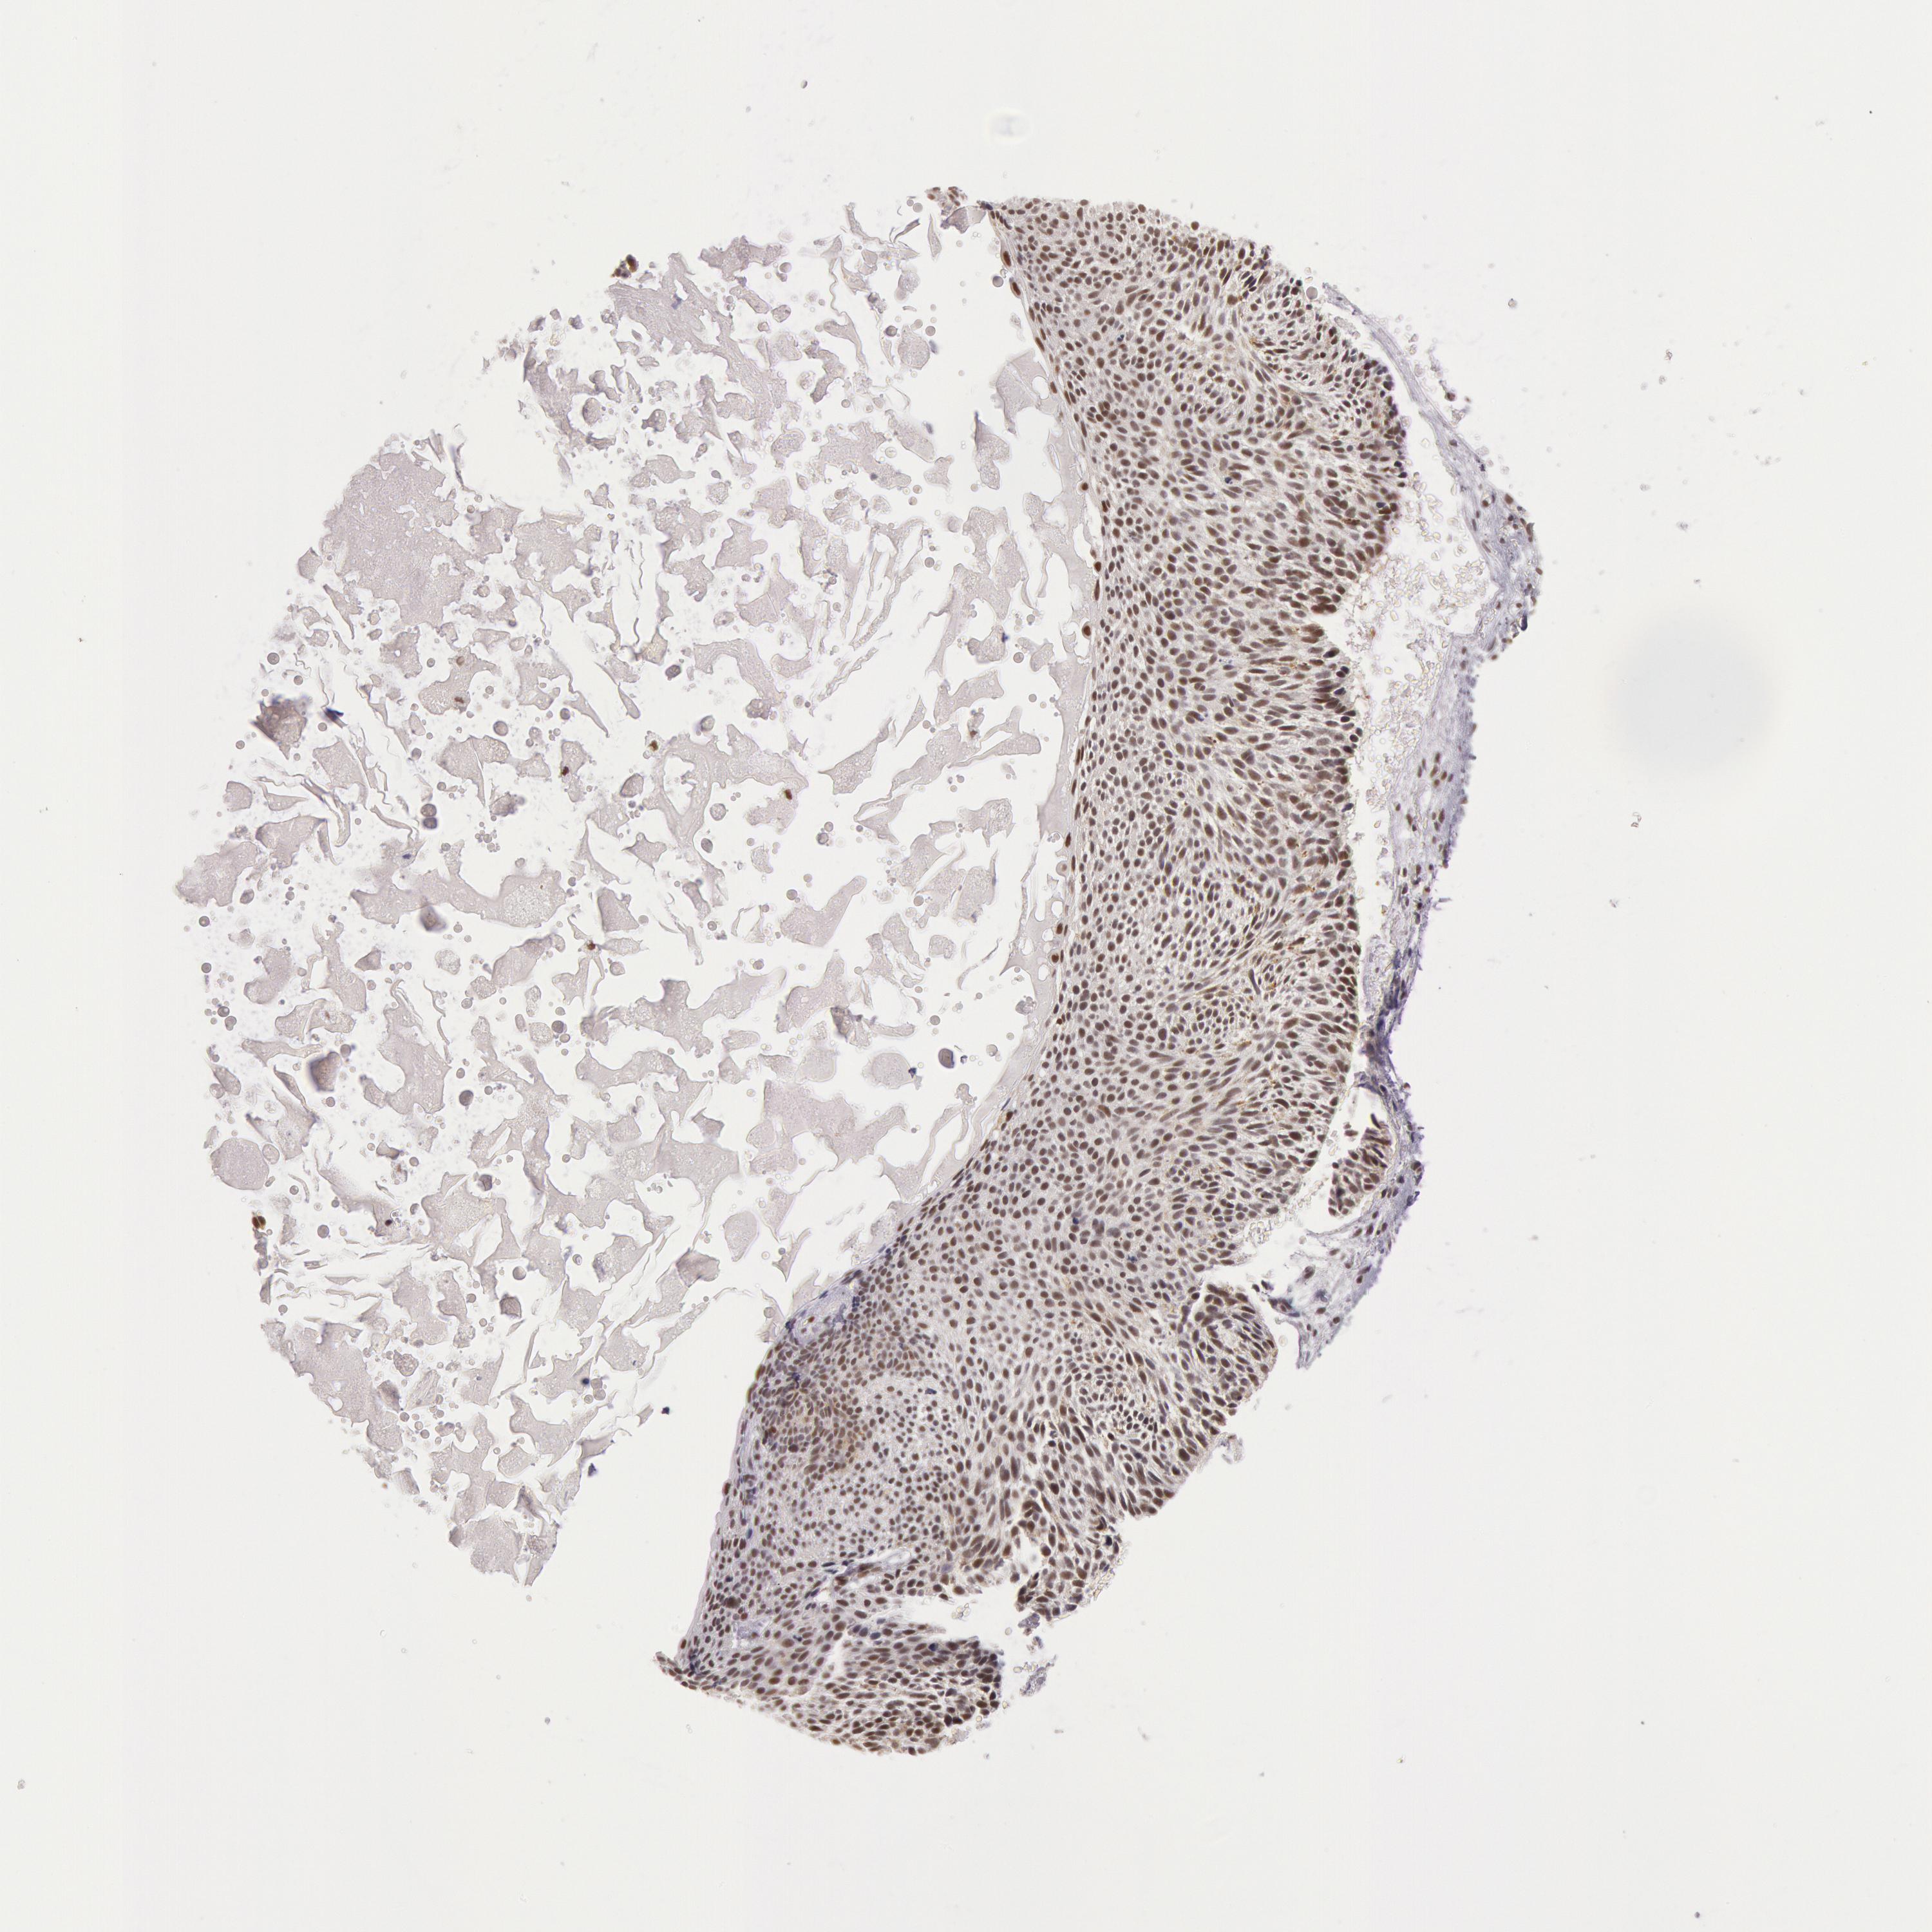

SKIN CANCER - Protein expressioni

A mouse-over function shows sample information and annotation data. Click on an image to view it in a full screen mode. Samples can be filtered based on level of antibody staining by selecting one or several of the following categories: high, medium, low and not detected. The assay and annotation is described here.

Antibody stainingi

Antibody staining in the annotated cell types in the current human tissue is reported as not detected, low, medium, or high, based on conventional immunohistochemistry profiling in selected tissues. This score is based on the combination of the staining intensity and fraction of stained cells.

Each image is clickable and will lead to virtual microscopy that enables deeper exploration of all samples and also displays staining intensity scores, fraction scores and subcellular localization as well as patient and tissue information for each sample.

Antibody HPA001221

Antibody HPA001222

Staining

High

Medium

Low

Not detected

Intensity

Strong

Moderate

Weak

Negative

Quantity

>75%

75%-25%

<25%

None

Location

Nuclear

Cytoplasmic/membranous

Cytoplasmic/membranous,nuclear

Squamous cell carcinoma, NOS

Basal cell carcinoma